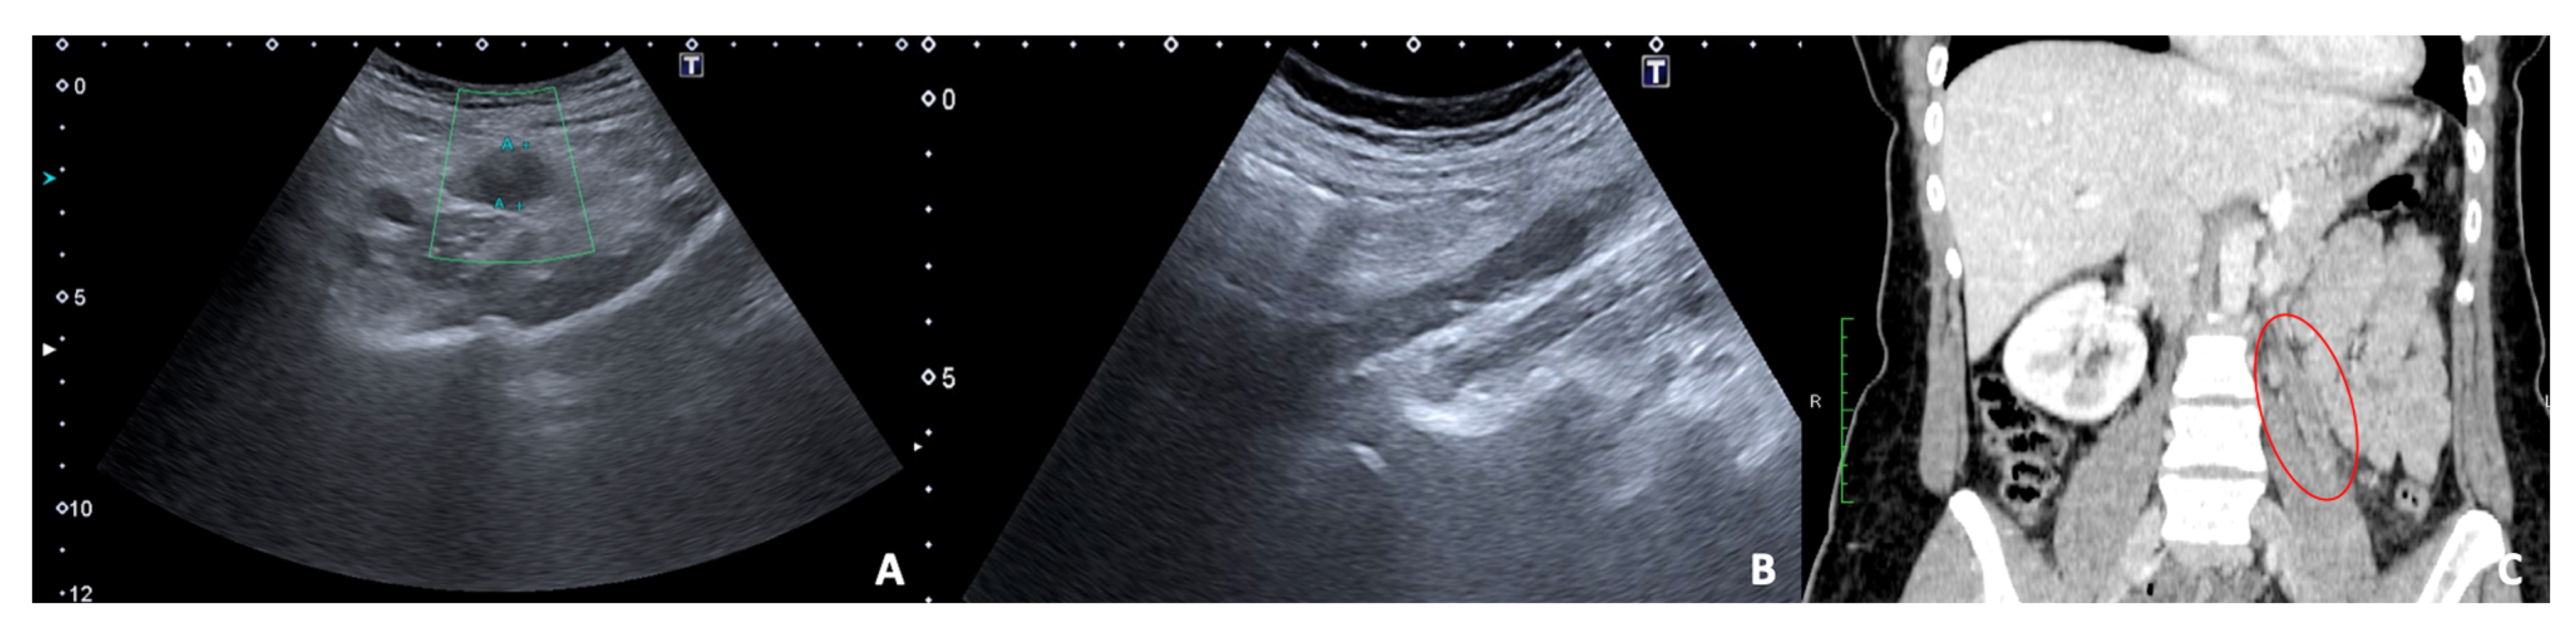

3.3. Uterine Leiomyoma

3.4. Endometriosis